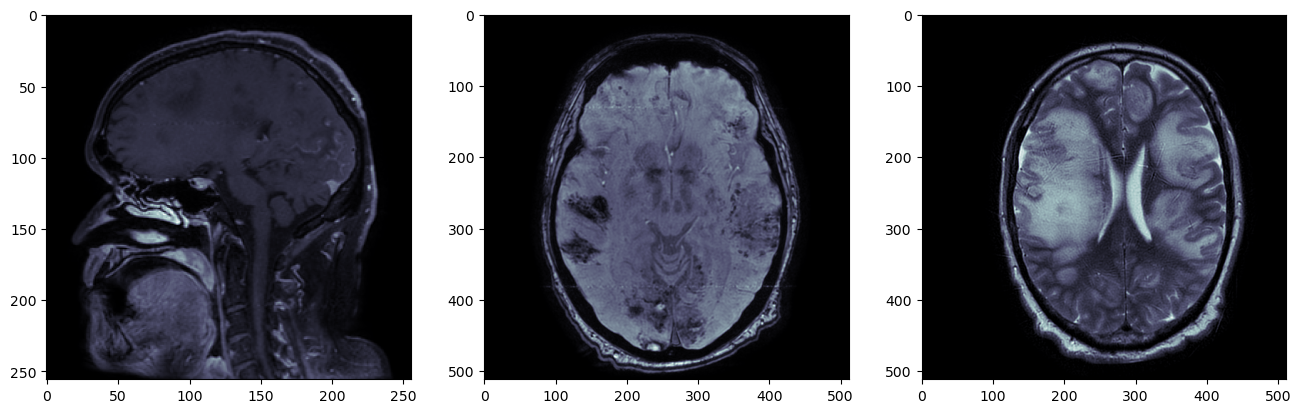

fig, axs = plt.subplots(nrows=1, ncols=3, figsize=(16,6))

axs[0].imshow(pydicom.dcmread(f'{resample_dir}/T1_CE/IMG-0003-00140.dcm').pixel_array, cmap='bone')

axs[1].imshow(pydicom.dcmread(f'{resample_dir}/SWI/IMG-0005-00046.dcm').pixel_array, cmap='bone')

axs[2].imshow(pydicom.dcmread(f'{resample_dir}/T2/IMG-0002-00030.dcm').pixel_array, cmap='bone')

Три серии